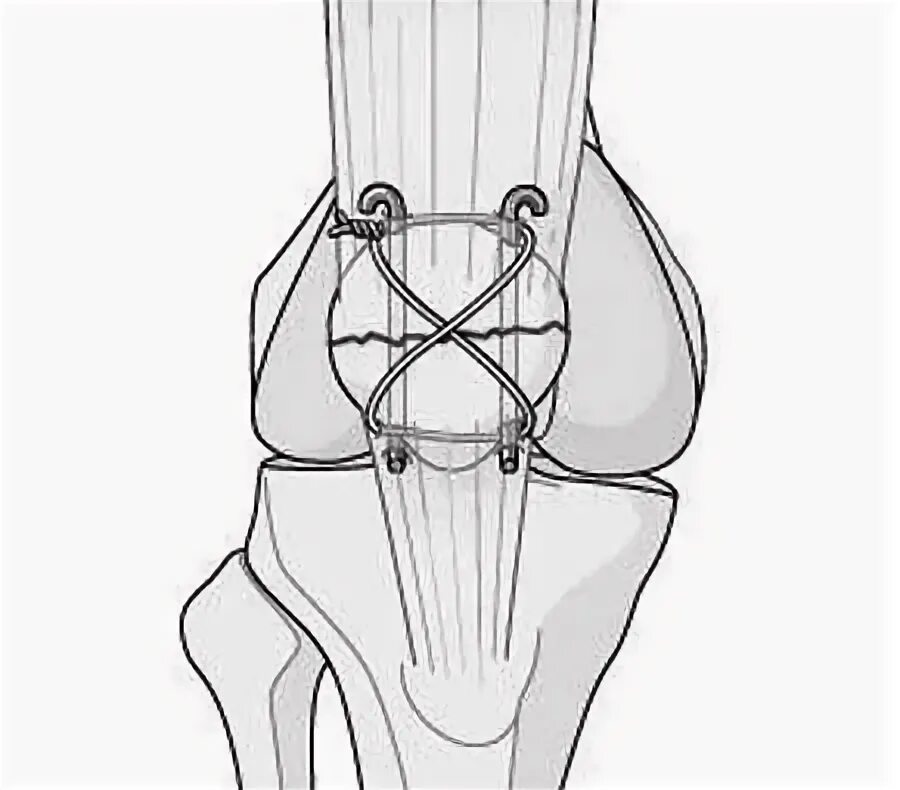

Перелом надколенника код по мкб 10